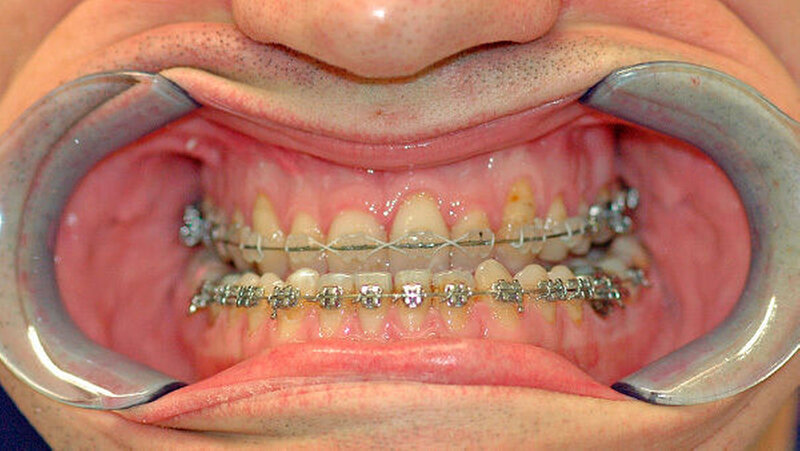

Das deutlich harmonischeres Profil drei Monate nach der Operation: Im Mai des nachfolgenden Jahres wurden die Metallplatten in einem ambulanten Eingriff wieder entfernt. Eine Multibandapparatur hält die Zähne noch "in der Reihe". Der Patient kann heute dank der individuellen innovativen Behandlung ein normales Leben führen, die Gesichtsästhetik und seine Kaufunktion sind vollständig wiederhergestellt.

Nach dreidimensionaler Planung im zahntechnischen Labor, in dem die Bissschlüssel konventionell hergestellt wurden, wurden dann ein Jahr später beide Kiefer operativ mobilisiert. Hierzu wurde von einem Schnitt im Mund der Oberkieferknochen freigelegt.

Mit einer Säge wurde ein gezielter Knochenschnitt durchgeführt. Nach der Präparation wurde der zahntragende Abschnitt des Oberkiefers vom restlichen Gesichtsschädel gelöst. Erst wurde die Bisssituation anhand des Bissschlüssels exakt eingestellt, dann mit 2 mm dicken Osteosyntheseplatten aus Titan der Knochen in der neuen Position mithilfe von Titanschrauben fixiert.

Die neue Position wurde mit einem zweiten Bissschlüssel, der die endgültige Bisssituation einstellt,zugeordnet und mit Osteosyntheseplatten und -schrauben gesichert. Die Operation ging mit einem stationären Aufenthalt von nur fünf Tagen einher.